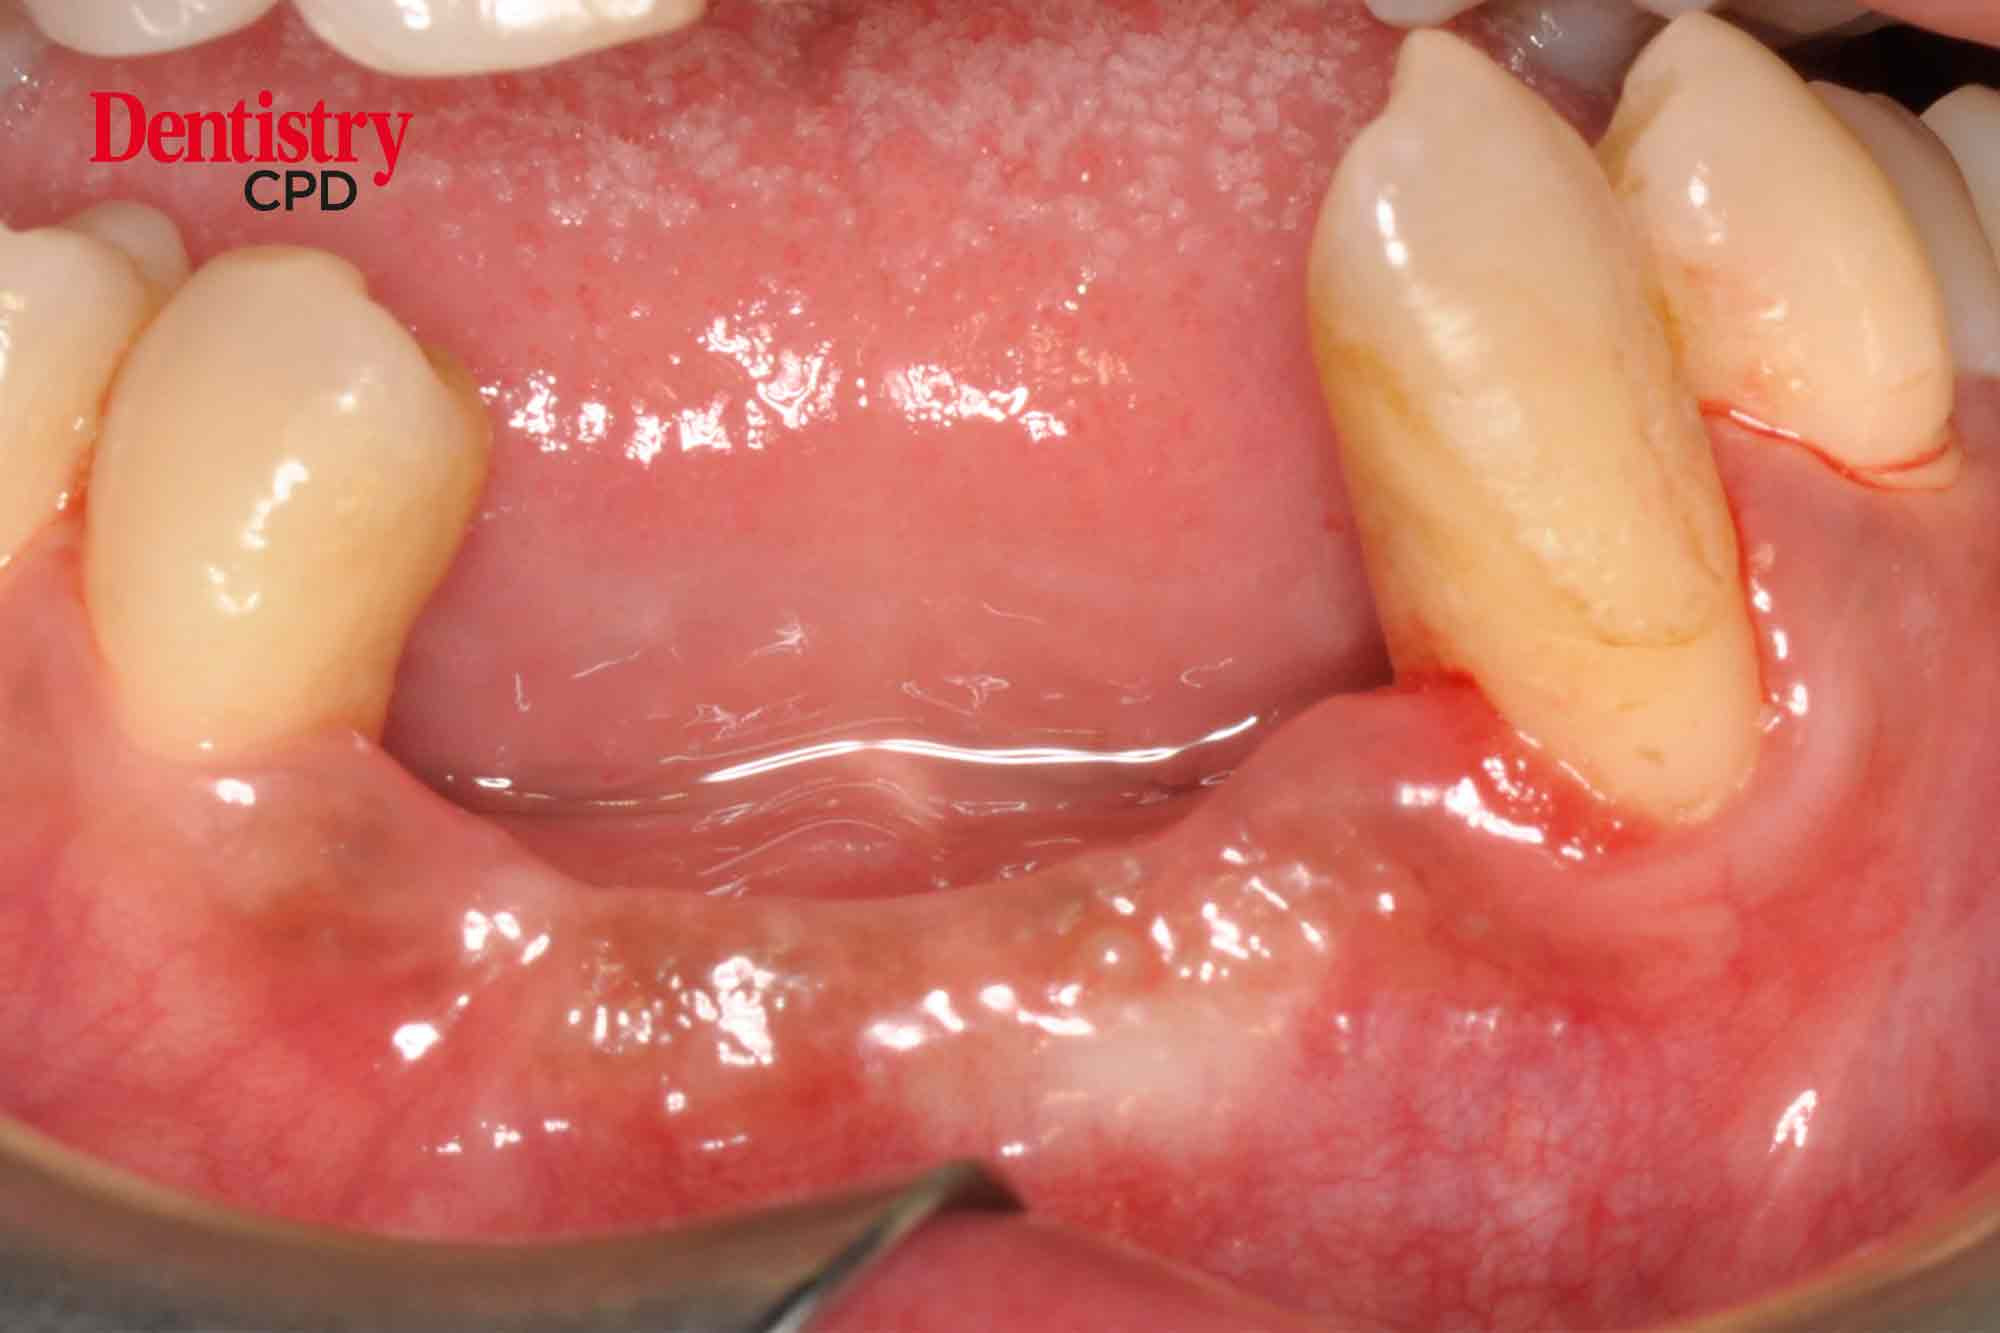

Chang IC Teoh describes the case management of an atrophic anterior mandible employing an alternative approach to autogenous tissue grafting

To describe the management of an atrophic anterior mandible, employing an alternative approach to autogenous tissue grafting.